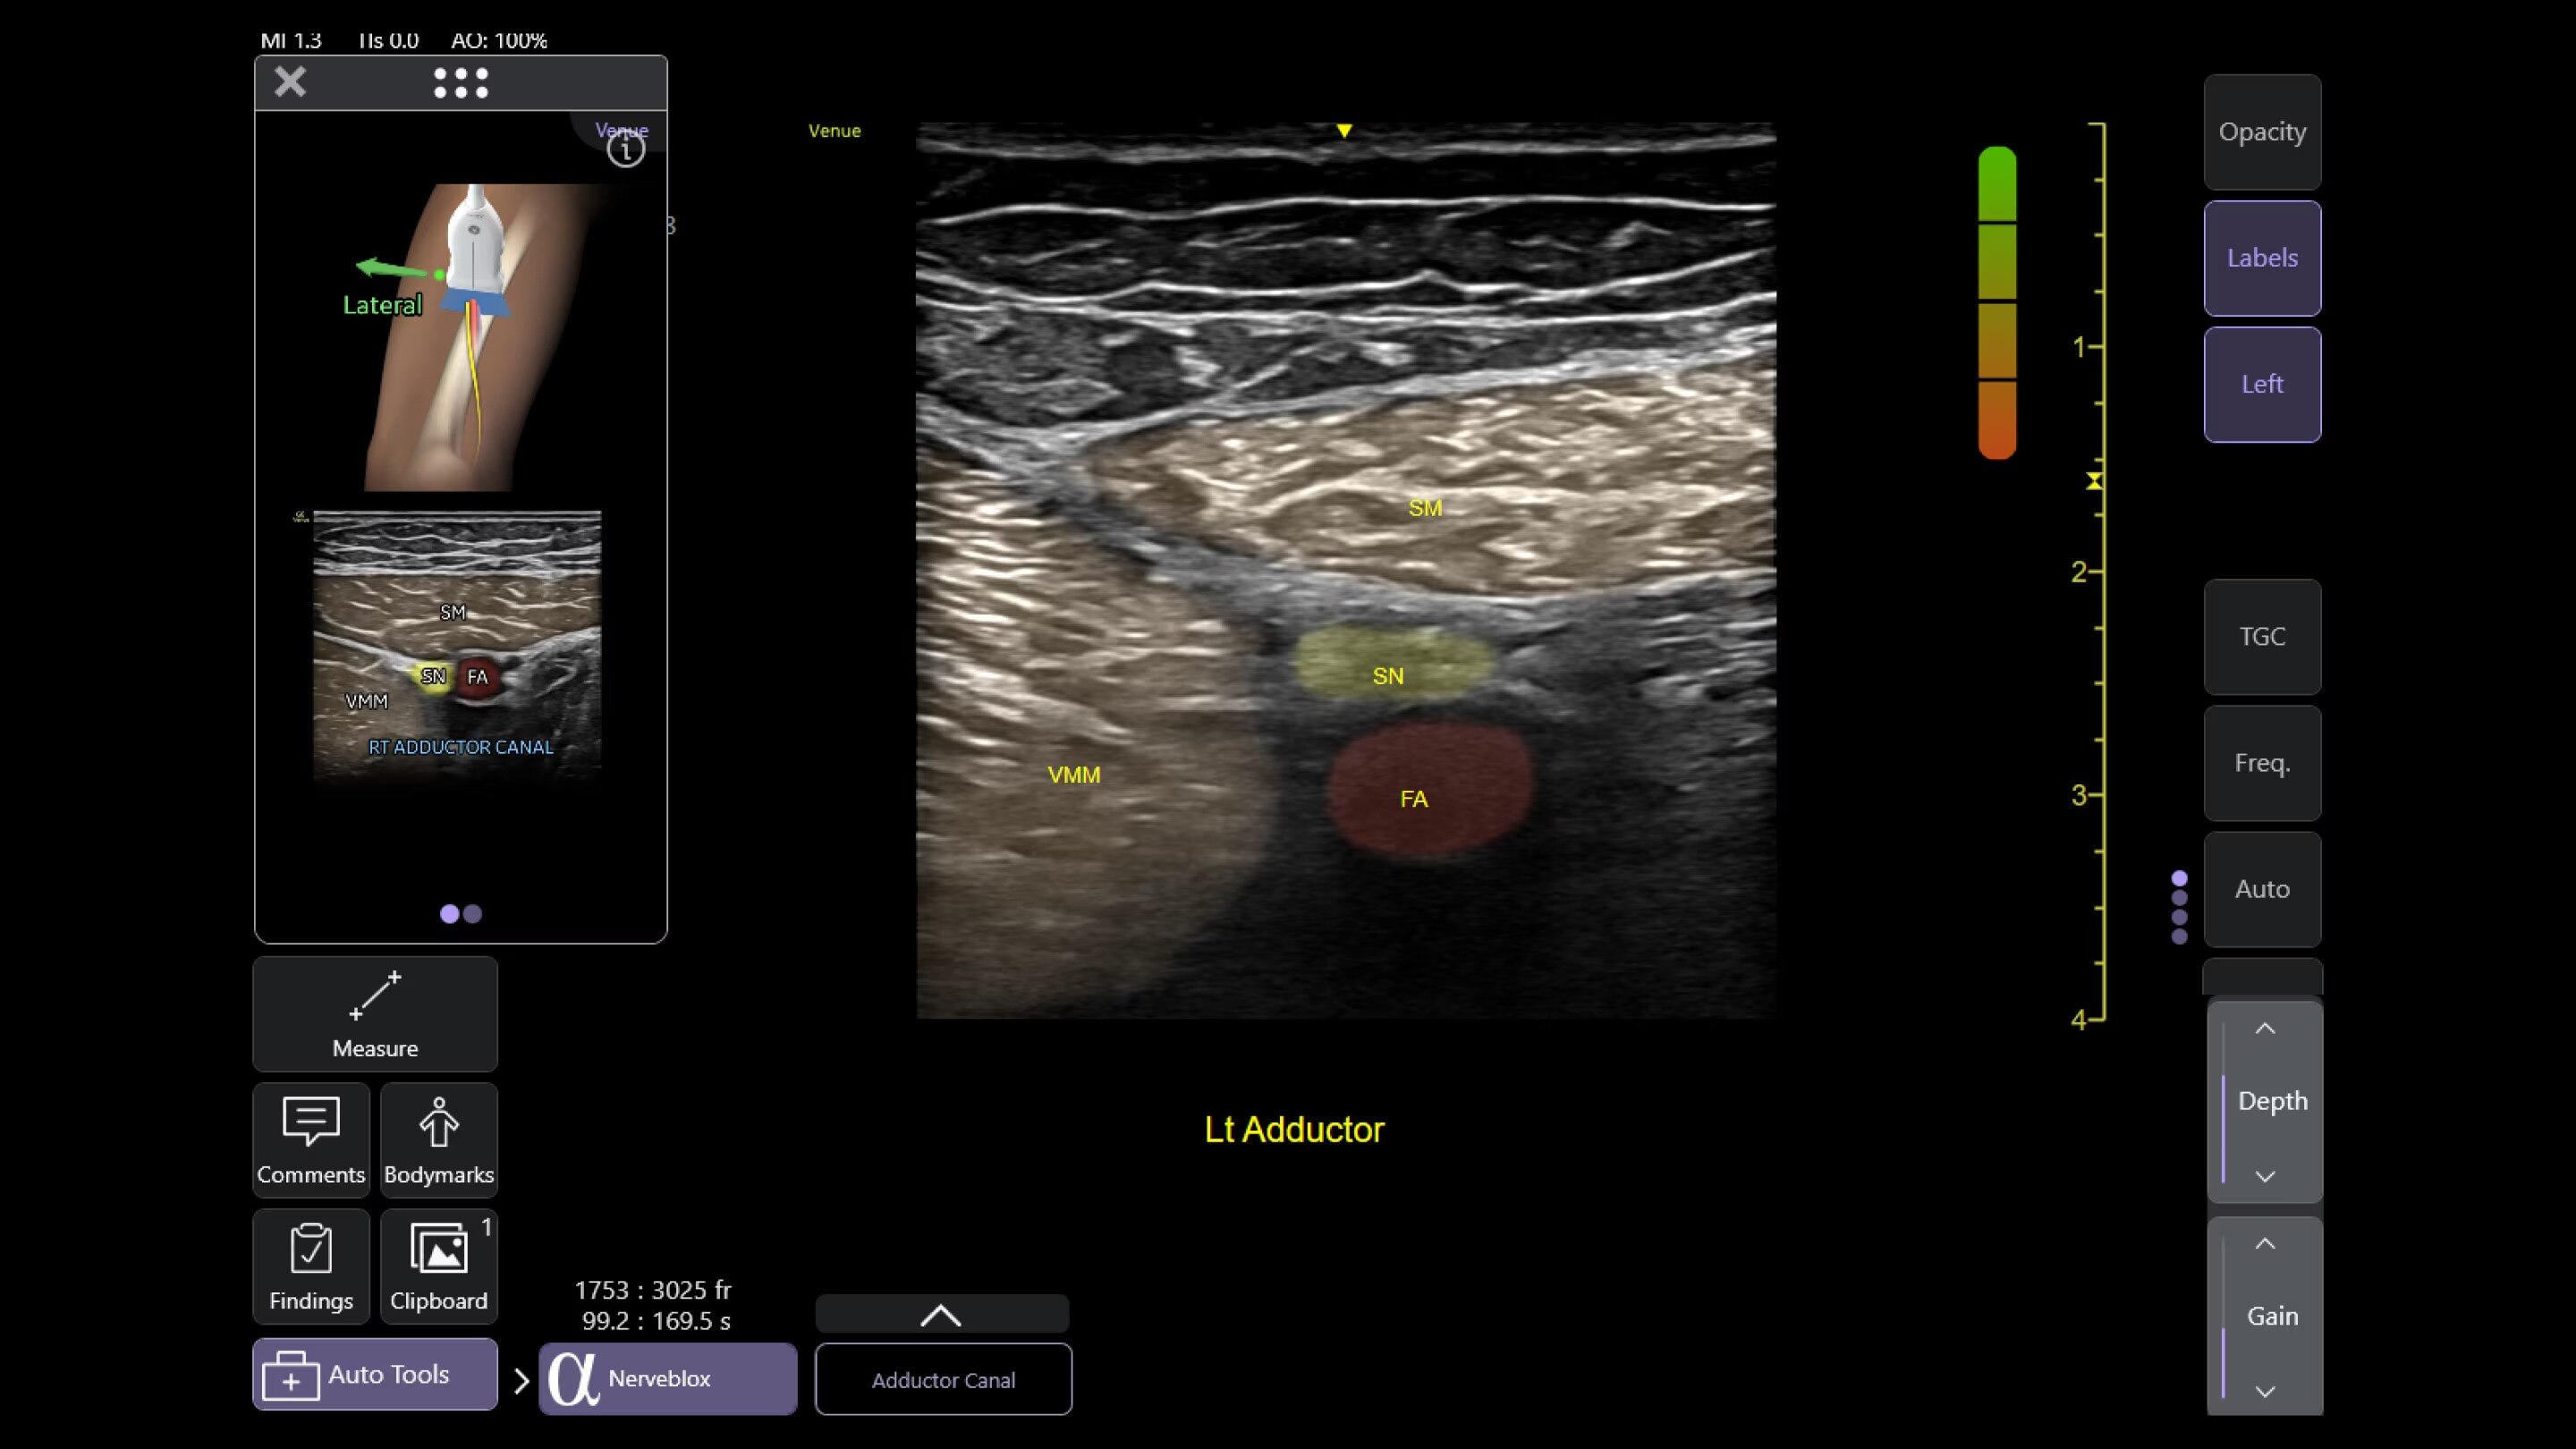

Needle recognition software helps with visualization for line placements

Catheter to Vessel Ratio

Accurate catheter selection tool

Selecting the wrong sized catheter can lead to catheter related thrombosis.3 Catheter to Vessel Ratio is a measurement tool that supports clinicians in selecting the appropriate sized catheter based on vessel diameter.